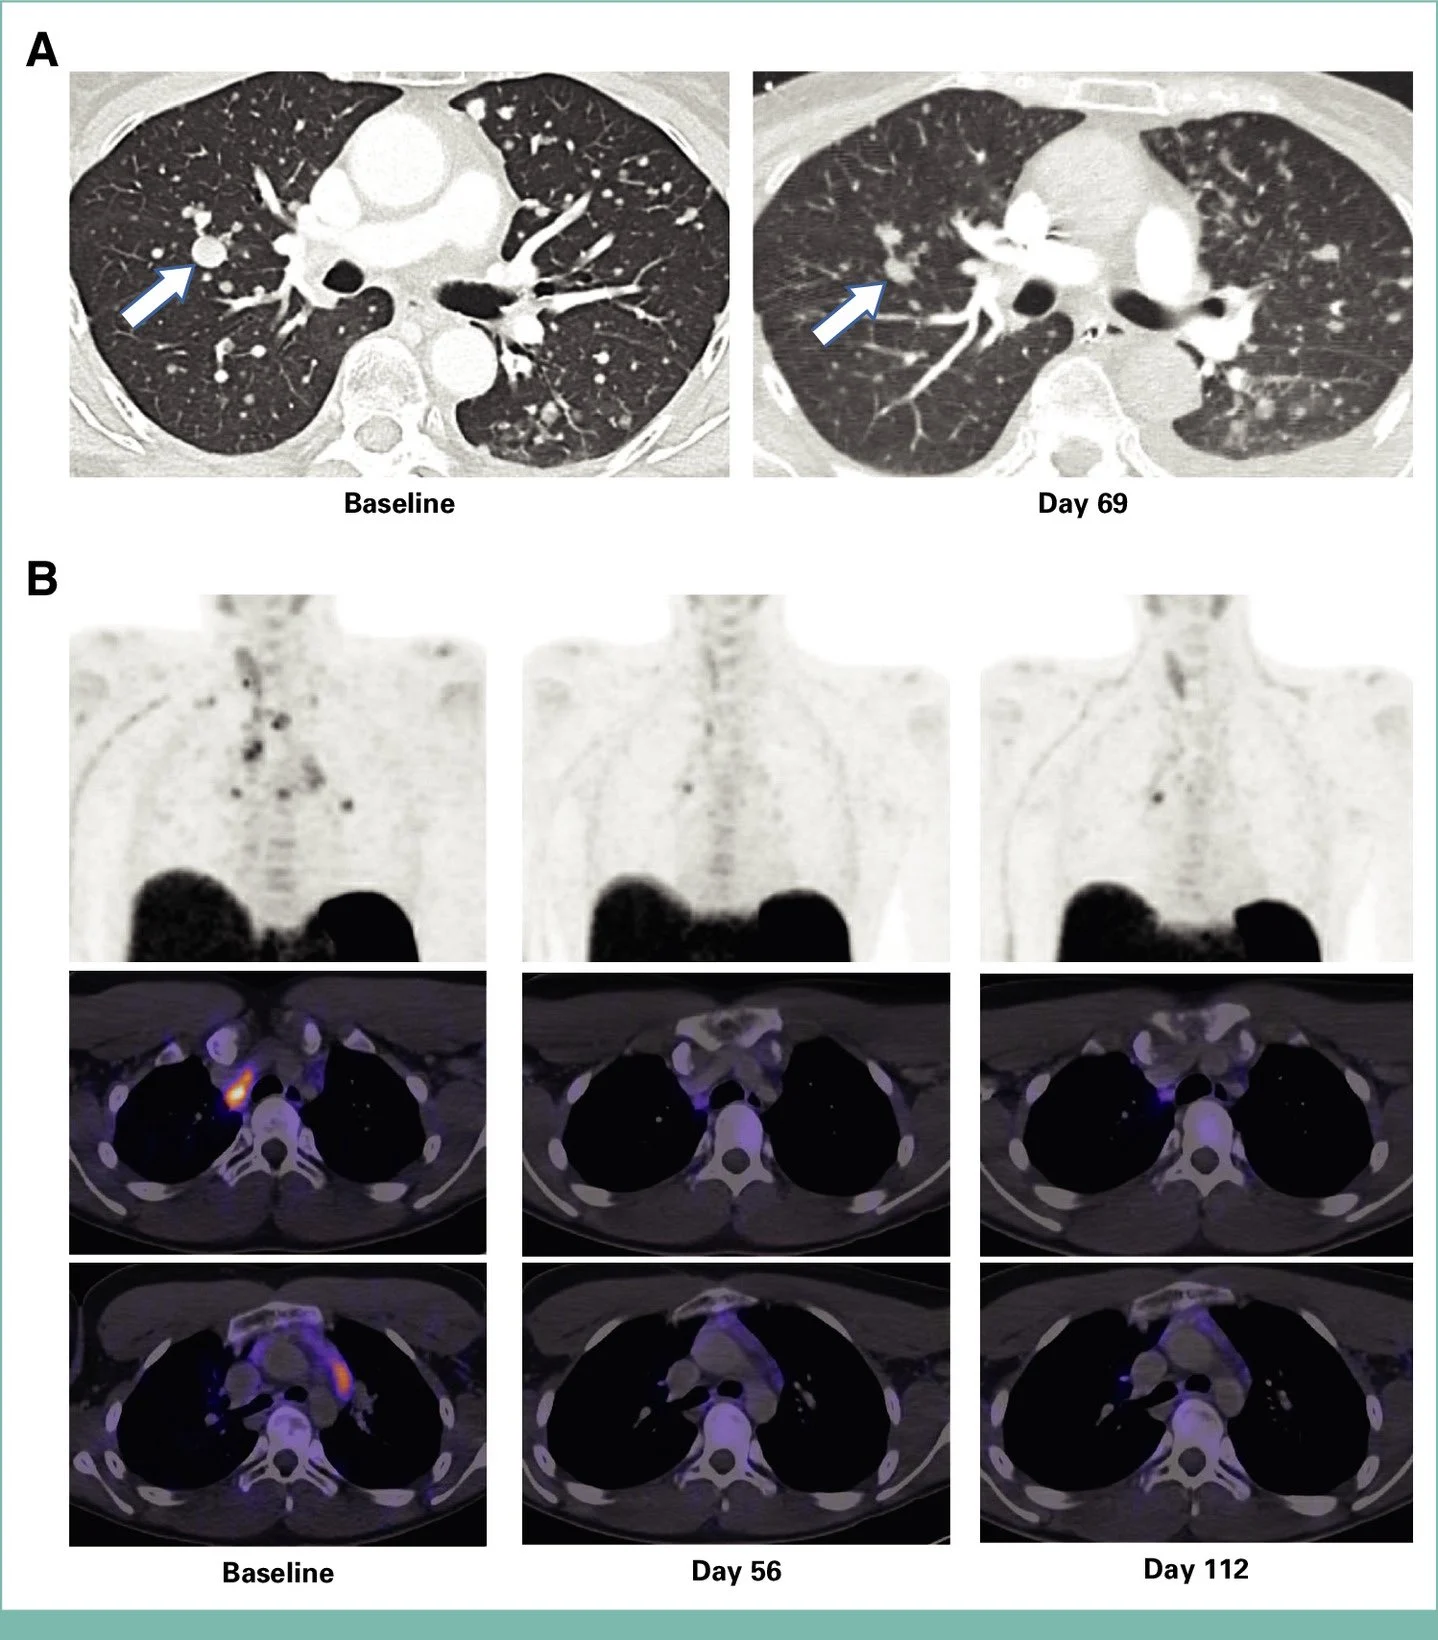

“Tarlatamab (DLL3) in MTC

- Case series (n=4): heavily pretreated MTC

- ORR 67% (2 PR, 1 SD evaluable)

- 100% clinical/biochemical activity signal

Title: Preliminary Safety and Efficacy of Tarlatamab in Medullary Thyroid Carcinoma